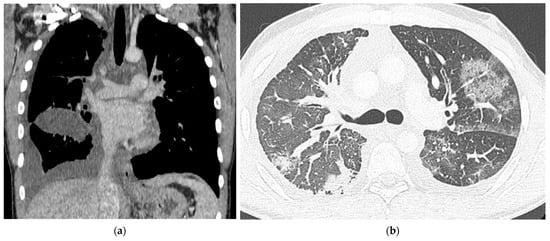

2. Case Report